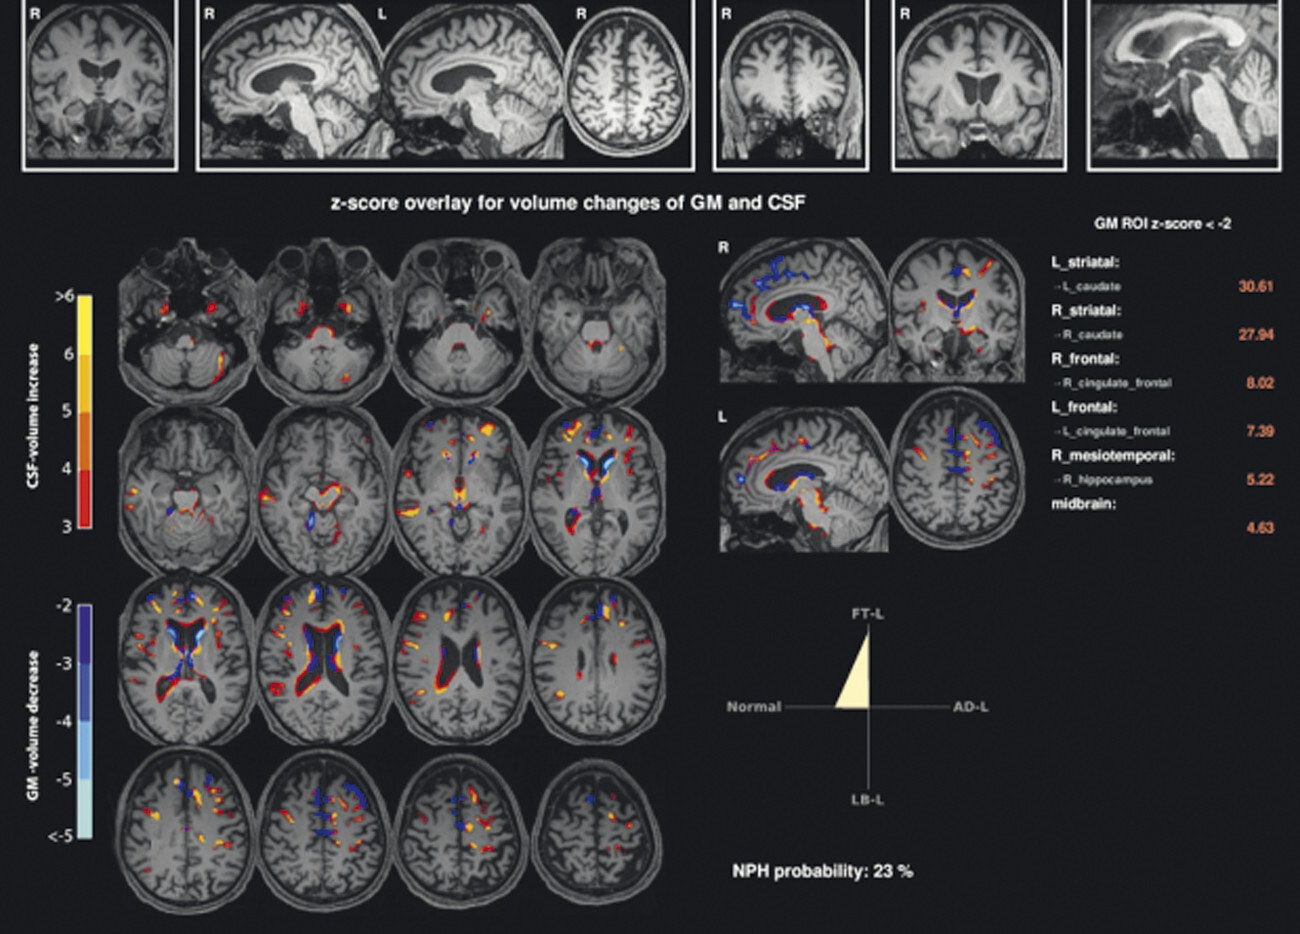

67-jährige Patientin mit über Jahre progredienter Verschlechterung des Gleichgewichts, Schluckstörungen und Sprechstörungen. In der T1w 3-D-Sequenz zeigt sich eine ausgeprägte Atrophie des Pons (a, Pfeil), der mittleren Kleinhirnstiele (b, Pfeile) und des Kleinhirns. Diese Veränderungen werden durch die Ganzhirnvolumetrie bestätigt (c): Anomale Regionen der grauen Substanz (mindestens 2 Standardabweichungen unter dem vergleichbaren Volumen des gesunden alters- und geschlechtsgematchten Normkollektivs) sind blau überlagert. Anomale Liquorvolumina (mindestens 2 Standardabweichungen über dem vergleichbaren Volumen des gesunden alters- und geschlechtsgematchten Normkollektivs) sind als rote bis gelbe Überlagerungen auf das individuelle Patientengehirn projiziert. MRT-morphologisch lässt sich somit die Verdachtsdiagnose Multisystematrophie vom zerebellären Prädominanztyp bestätigen.

a Sagittale T1w 3-D-MRT-Sequenz.

b Axiale T1w 3-D-MRT-Sequenz.

c Voxel- und regionenbasierte Analyse.

55-jähriger Patient mit vor 13 Jahren diagnostiziertem, rechtsbetontem idiopathischem Parkinson-Syndrom vom hypokinetisch-rigiden Typ. Überweisung zur Indikationsstellung für eine tiefe Hirnstimulation. Hauptprobleme sind Stürze (ca. 20 in den letzten 6 Monaten) und eine ausgeprägte Dysarthrophonie. Keine psychiatrischen Auffälligkeiten. Demenzielle Entwicklung seit ca. einem Jahr. In der T1w 3-D-Sequenz zeigt sich eine ausgeprägte Putamenatrophie beidseits (a, Pfeile). Visuell ist vor allem der Sulcus parietooccipitalis erweitert (b, Pfeil). In der Ganzhirnvolumetrie sind eine darüber hinausgehende parietookzipitale und eine zerebelläre, jedoch keine Ponsatrophie zu erkennen (c). Klinisch und MRT-morphologisch handelt es sich also nicht um ein idiopathisches Parkinson-Syndrom, sondern um eine Multisystematrophie vom Parkinson-Prädominanztyp.